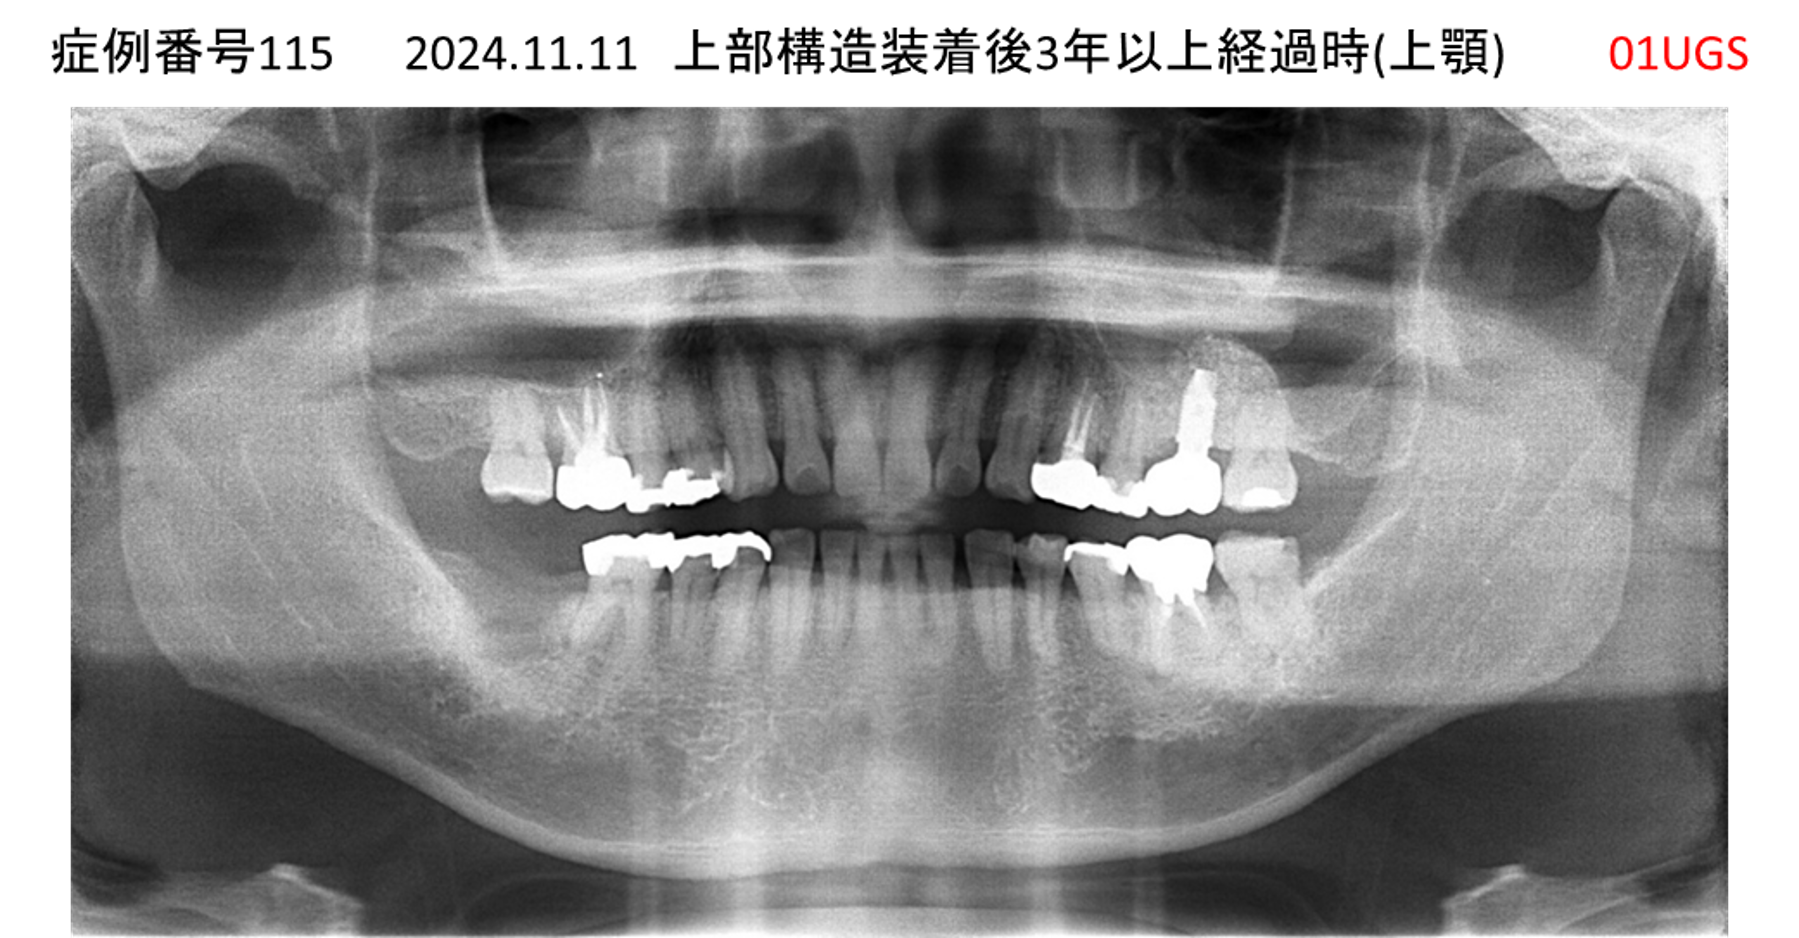

上の前歯が揺れてきてかめない患者様のインプラント症例

| 治療名称 |

インプラント |

| 治療費用 |

335万円+税 |

| 治療期間 |

4か月 |

| 患者さんの症状(主訴) |

上の前歯が揺れてきて噛めない |

| 治療内容 |

サイナスリフト 抜歯即時インプラント |

| 治療結果 |

ちゃんと噛めるようになった。不安がなくなった。見た目がとても良くなったのすごくうれしい。 |

| 治療の注意点(リスク/副作用) |

インプラントが壊れたら再治療が必要 |